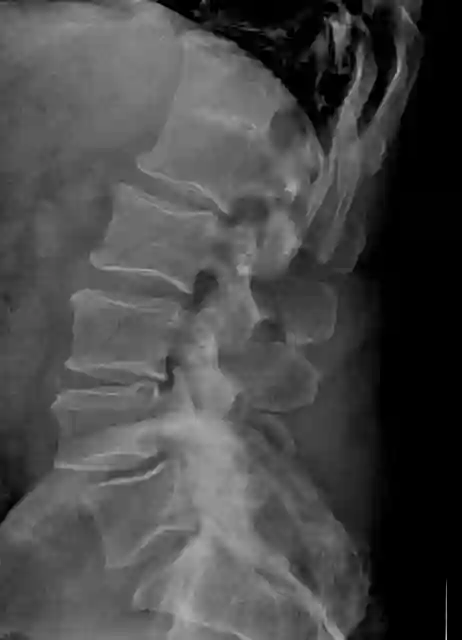

Blockwirbelbildung im Röntgen

Darstellung eines Blockwirbels zwischen LWK1 und BWK12 in einem lateralen Röntgenbild.